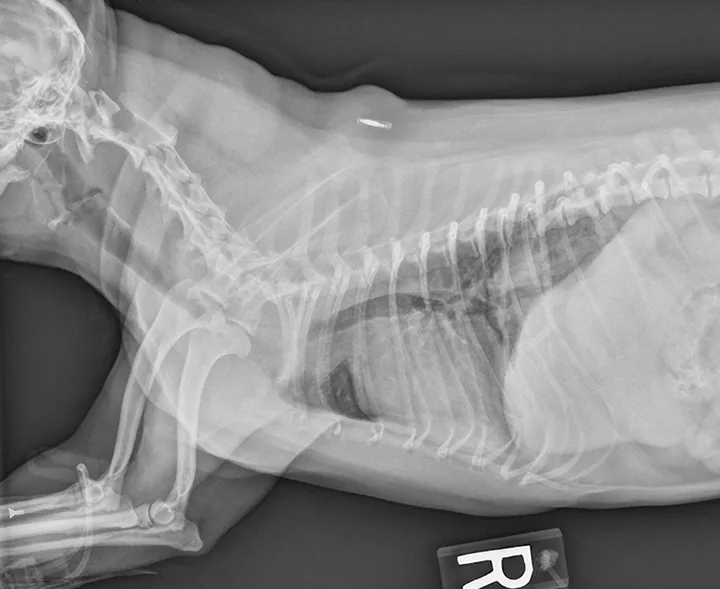

Patients that are severely affected, are refractory to medical management alone, or have life-threatening airway obstruction often benefit from placement of a self-expanding intraluminal tracheal stent (Figure 2). Most patients improve substantially, and survival rates are high; however, most patients require continued medical management.

FIGURE 2 Radiograph of a patient with tracheal collapse treated with a fully deployed intraluminal tracheal stent